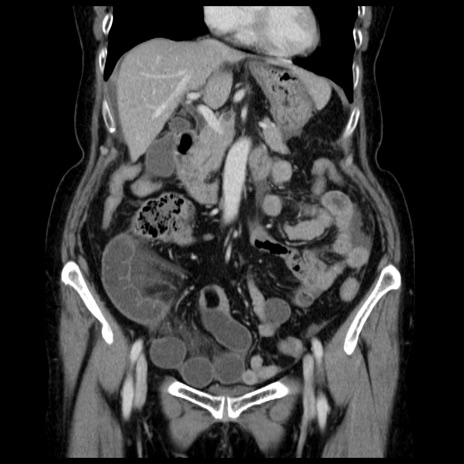

症例13(冠状断像)

【症例】70歳代女性

【主訴】腹痛、嘔吐

【現病歴】15時間程前(昨晩)より腹痛あり。今朝になっても症状の改善なく、嘔吐あり。腹痛も増悪あり、救急外来受診。

【既往歴】子宮癌全摘術後

【身体所見】意識清明、BP 121/72mmHg、P 74bpm、SpO2 100%(RA)、腹部:平坦・軟、腸雑音ほぼ聴取せず。下腹部・心窩部・臍左上に圧痛あり。反跳痛なし。

【データ】WBC 10600、CRP 0.15